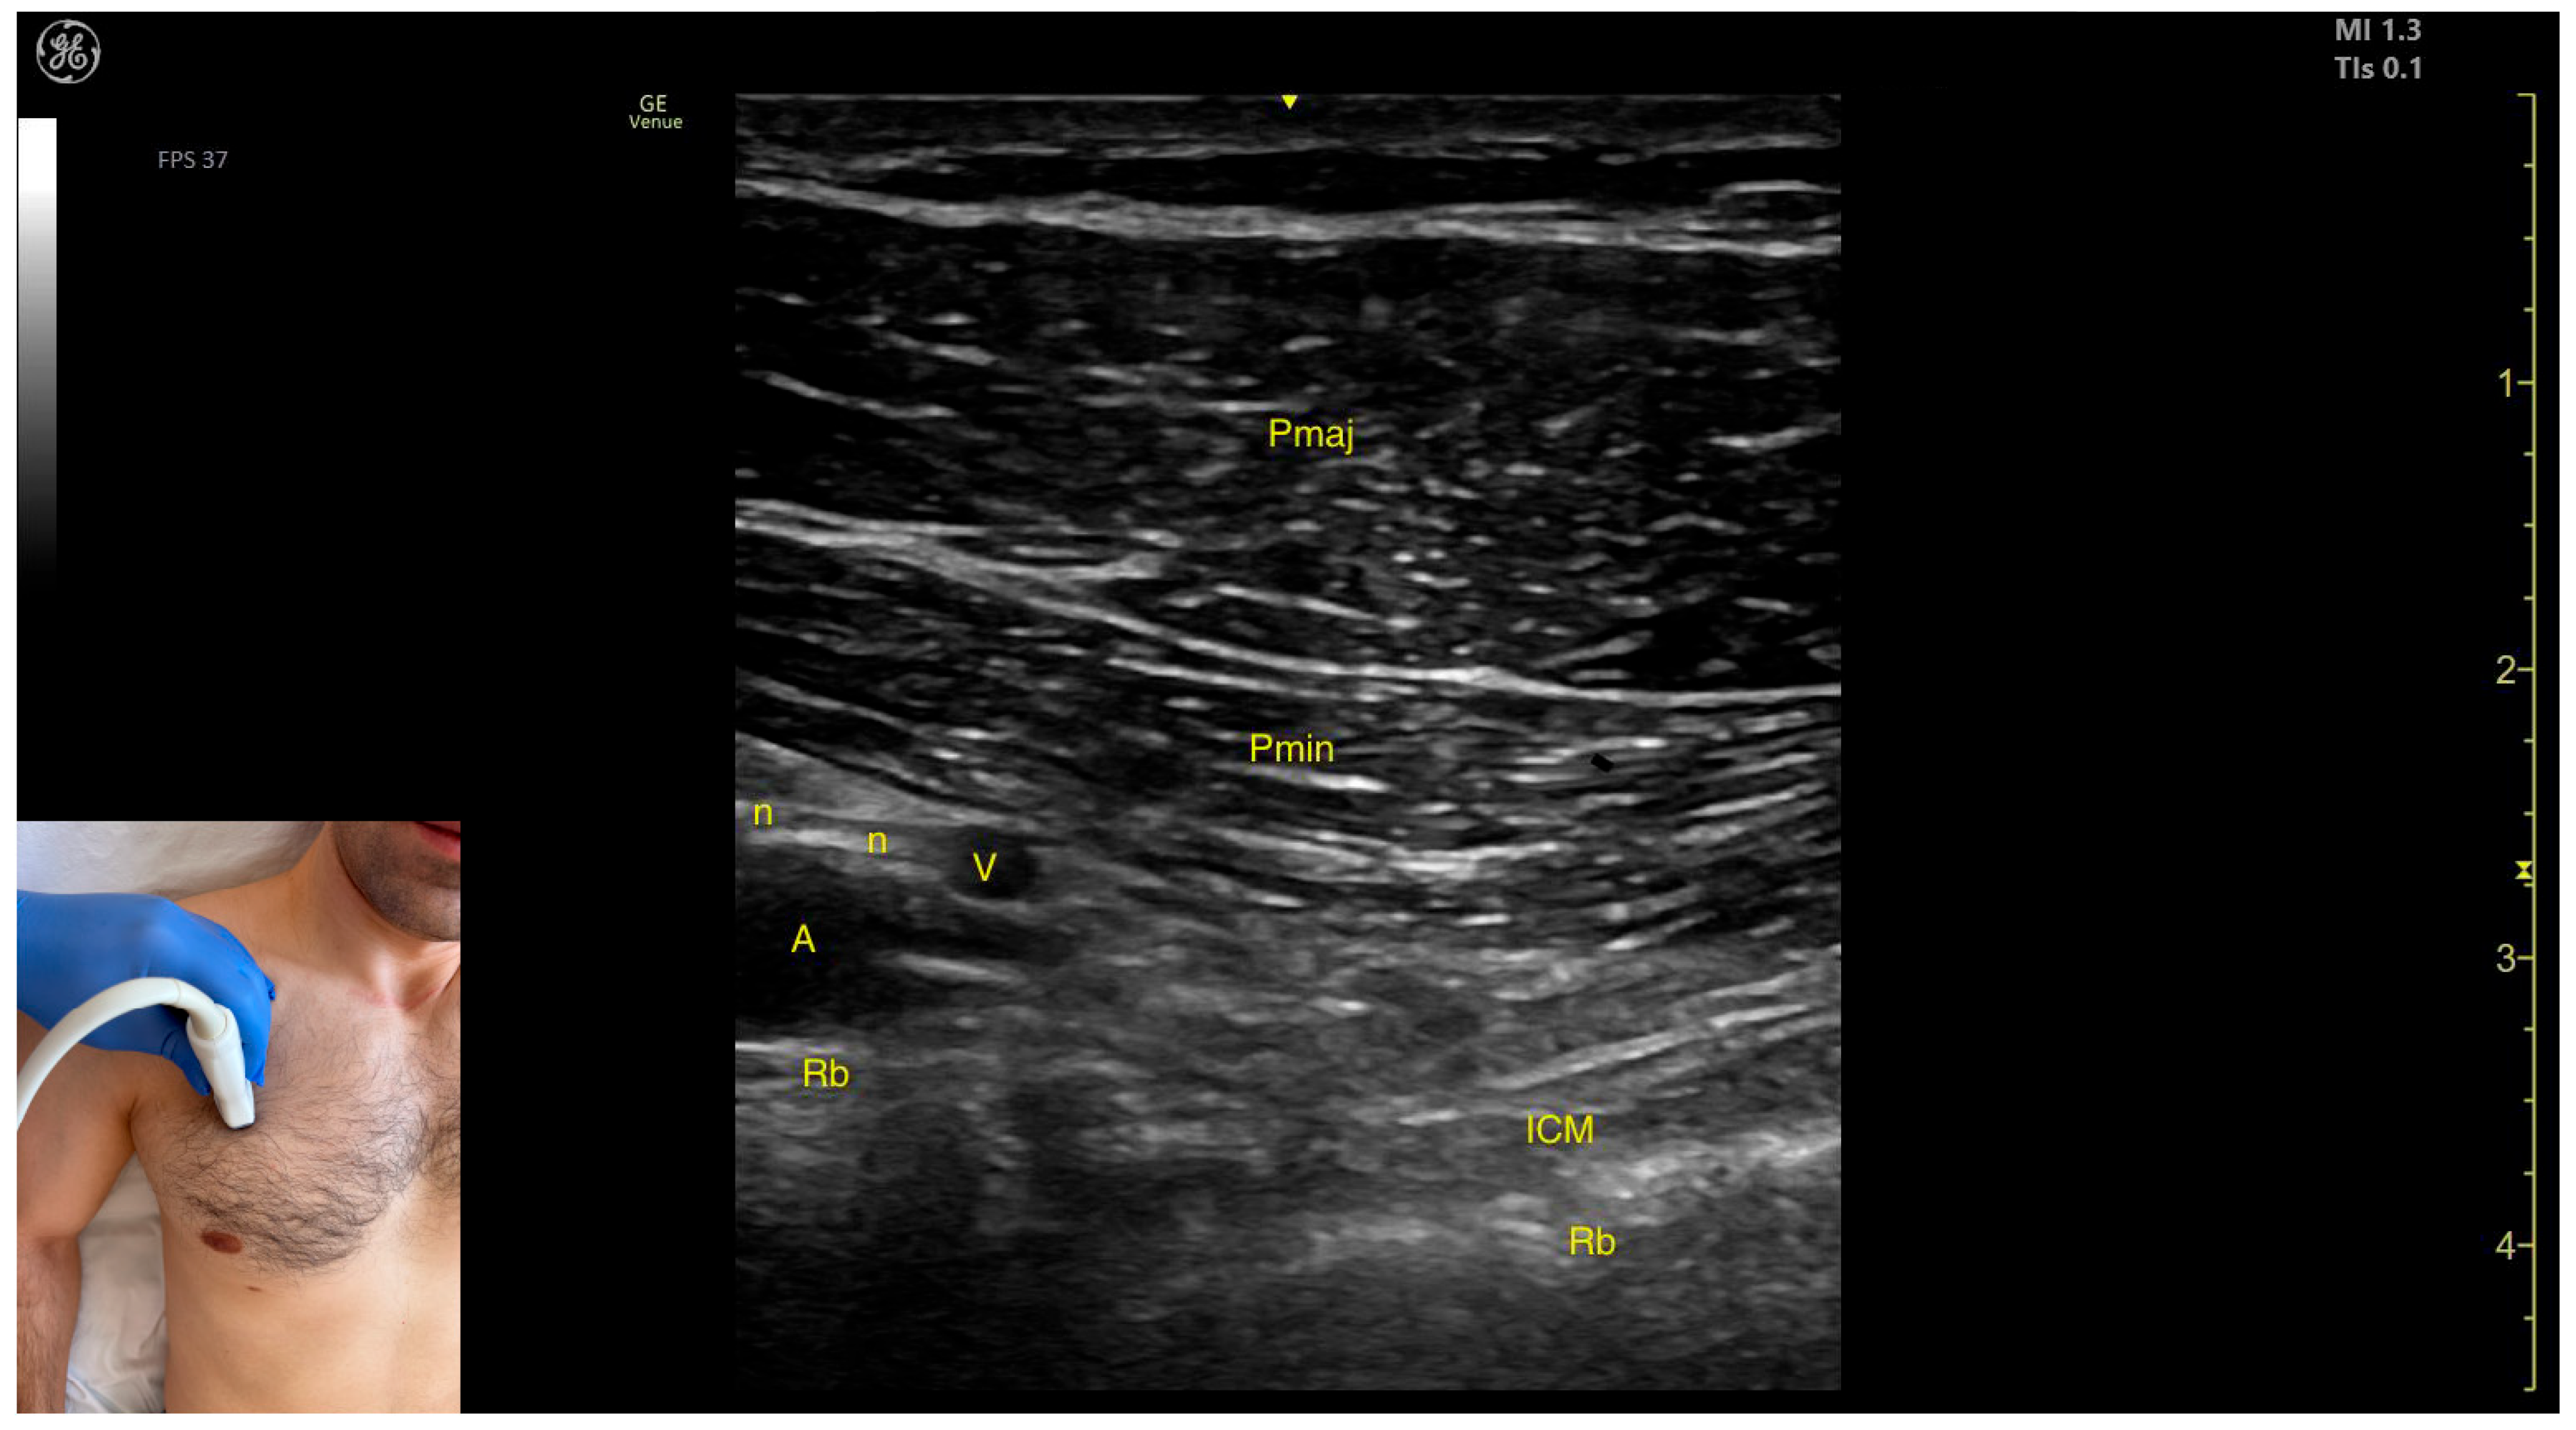

- The pectoralis minor (Pmin) muscle;

- The pectoralis major (Pmaj) muscle.

2.4.3. Key Ultrasound Landmarks

- Muscle morphology: The muscle has two heads that can be approached individually: the clavicular head (PMC), located laterally, and the sternocostal head (PMS), located medially. An intramuscular fascia (IMF) separates the two heads.

- External fascia: The Pmaj presents a pronounced fascia that clearly separates it from the subcutaneous plane and the Pmin during BoNT-A injections.

- Neurovascular landmark: The lateral pectoral nerve often courses alongside the thoracoacromial artery within the fascia separating P maj and P min. This can be targeted during diagnostic nerve blocks to distinguish reducible from non-reducible shoulder deformities in severe spasticity.

- Dynamic evaluation: During dynamic evaluation, scanning toward the humeral insertion reveals a gradual reduction in muscle thickness for both heads until they transform into tendons. Muscle contraction is visible during adduction and internal rotation maneuvers of the upper limb at the shoulder joint [19].

2.4.4. Clinical Implications and Injection Strategy

- For the clavicular head, the transducer is placed at a 45-degree angle toward the axilla, along the midclavicular line, approximately 2 cm from the clavicle.

- For the sternocostal head, the transducer is positioned longitudinally along the midclavicular line, about 5 cm distal to the clavicle.

- Muscle position: It represents the first muscle mass located superficial to the rib cortex and intercostal muscles at this level. Superficial to the Pmin, the Pmaj muscle is observed. Deep to the Pmin, the axillary artery and vein, along with distal nerve branches from the brachial plexus, are visible.

- External fascia: The Pmin has a pronounced fascia that separates it from the Pmaj during BoNT-A injections.

- Dynamic evaluation: During dynamic evaluation, scanning proximally toward the coracoid process of the scapula shows a decrease in muscle thickness until the muscle transforms into a tendon [37].